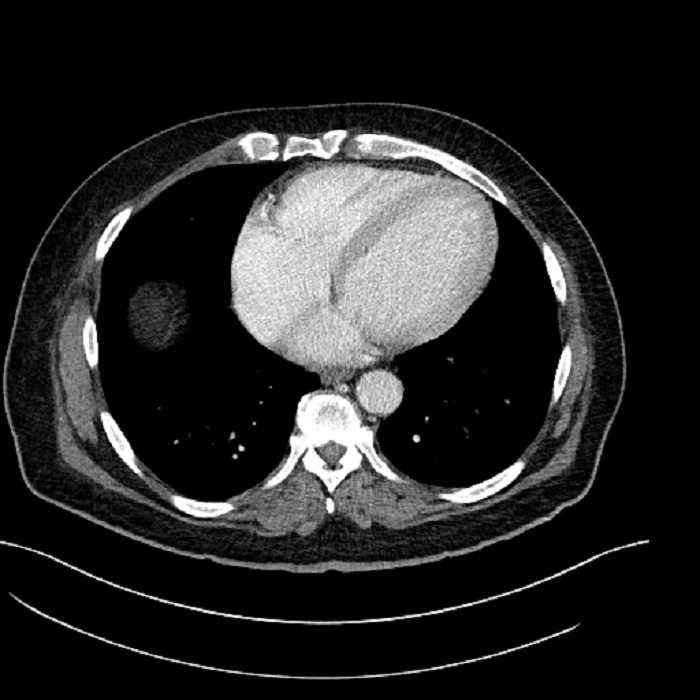

• Lower chest

• Mild cardiomegaly

• Mild dependent atelectasis

• Hepatic abscess

Acute sigmoid diverticulitis complicated by a small contained perforation and a large abscess in the right hepatic lobe. Additional small subcapsular abscesses along the anterior margin of the left hepatic lobe.

• The classic CT imaging appearance is a double target sign with internal low density surrounded by an internal enhancing rim (capsule) and a low density external rim (edema)

Hepatic abscess showing the double target sign with low density internally surrounded by a thin inner enhancing rim (red arrow) and ill-defined outer low density rim (yellow arrow). Blue arrow indicates an internal septation. Red arrows: additional smaller subcapsular abscesses. Red arrow: focal contained perforation associated with diverticulitis.